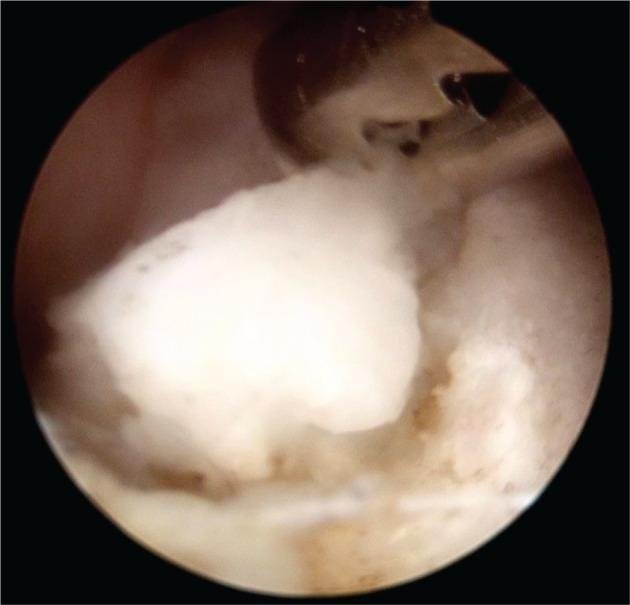

Medial elbow pain.

Medial elbow pain is uncommon when compared with lateral elbow pain.Medial epicondylitis is an uncommon diagnosis and can be confused with other sources of pain.Overhead throwers and workers lifting heavy objects are at increased risk of medial elbow pain.Differential diagnosis includes ulnar nerve disorders, cervical radiculopathy, injured ulnar collateral ligament, altered distal triceps anatomy or joint disorders.Children with medial elbow pain have to be assessed for 'Little League elbow' and fractures of the medial epicondyle following a traumatic event.This paper is primarily focused on the differential diagnosis of medial elbow pain with basic recommendations on treatment strategies. Cite this article: EFORT Open Rev 2017;2:362-371. DOI: 10.1302/2058-5241.2.160006.